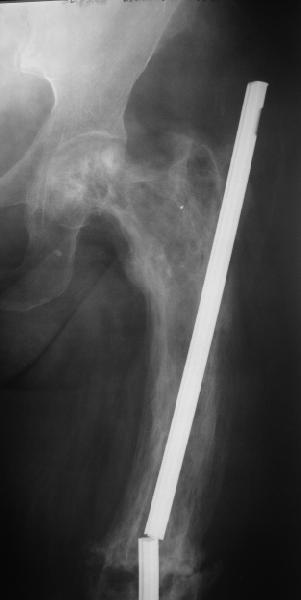

бывали ли у кого-нибудь такие случаи Уважаемые коллеги, вчера прооперировал женщину 60 лет с болезнью Педжета, переломом верхней трети бедра. Выявлена в августе этого года, сломала три дня назад от небольшого усилия. Из сопутствующих болезней лейкоз, сахарный диабет. Бывали ли кого-нибудь такие случаи, чем это все заканчивалось?

Стержень можно было бы поставить подлиннее.